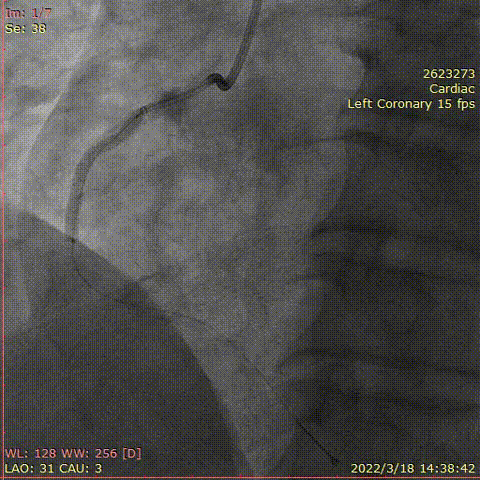

冠脉造影

对前降支行IVUS,钙化较重,超声导管通过困难